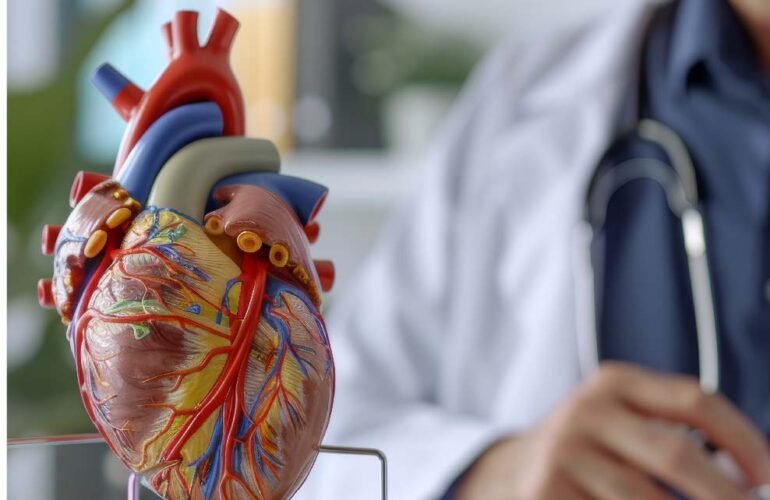

Northern Heart Hospital: Pusat Keunggulan Perawatan Jantung

Northern Heart Hospital: Pusat Keunggulan Perawatan Jantung Selamat datang di Northern Heart…

How Your Heart Doctor Protects Your Cardiovascular Health

How Your Heart Doctor Protects Your Cardiovascular Health Cardiovascular health is fundamental…